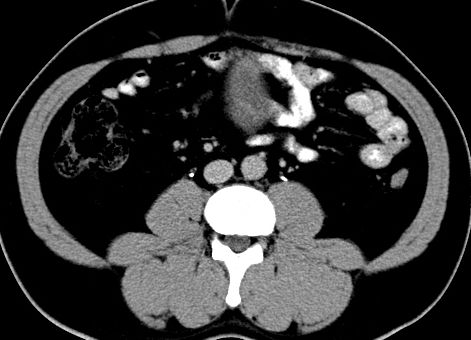

(腹腔)神经鞘瘤

男,48岁,间断性下腹不适1年。

手术探查

:距回盲部28厘米处肠系膜根部可见5*7cm左右包块,质中等硬度,活动度尚可,肝、胆、胰、脾肾未见明显异常。

病理

:(腹腔)

神经鞘瘤

,伴出血、坏死及囊性变,伴淋巴结反应性增生。

免疫组化结果

:sma(-), desmin(-), cd117(-), s-100(+++), nf(-),vimentin(+++).